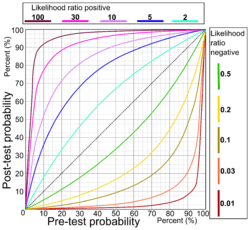

Relation between pre-and post-test probabilities for various likelihood ratio positives (upper left half) and various likelihood ratio negatives (lower right half).